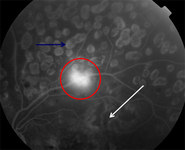

Fluorescein angiogram in proliferative diabetic retinopathy: new vessels on the optic disc (red arrow), capillary non-perfusion (red rectangle), microaneurysms (green circle), venous beading (blue arrow), intraretinal microvascular abnormalities (yellow arrow)

Courtesy of Moorfields Photographic Archive; used with permission